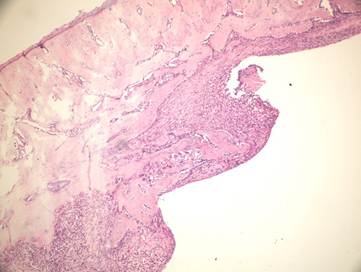

Figure 4

Newly formed bone in group +4°C (H&E x100)

Although there was no statistically significant difference between the group irrigated with 25°C and 4°C saline for new bone formation, latter group had numerous osteoblasts and more prominent osteoblastic rim around the trabeculae of new bone (Figures 4,5). These results indicate that there is no disadvantage to use 25°C saline irrigation, but it may be better to use 4°C saline irrigation for rapid healing.

In the present study we evaluated the specimens in terms of new bone formation, presence of infection, necrosis and fibrosis Our study demonstrated significant difference regarding the necrosis values between control group (without irrigation) and the group irrigated with 25°C and 4°C saline (Figures 4-6). Necrosis was not observed in second and third groups. However copious saline irrigation was useful for cleaning the operation area from any remnants of the drill. It is thought that this can be an advantage for wound healing.